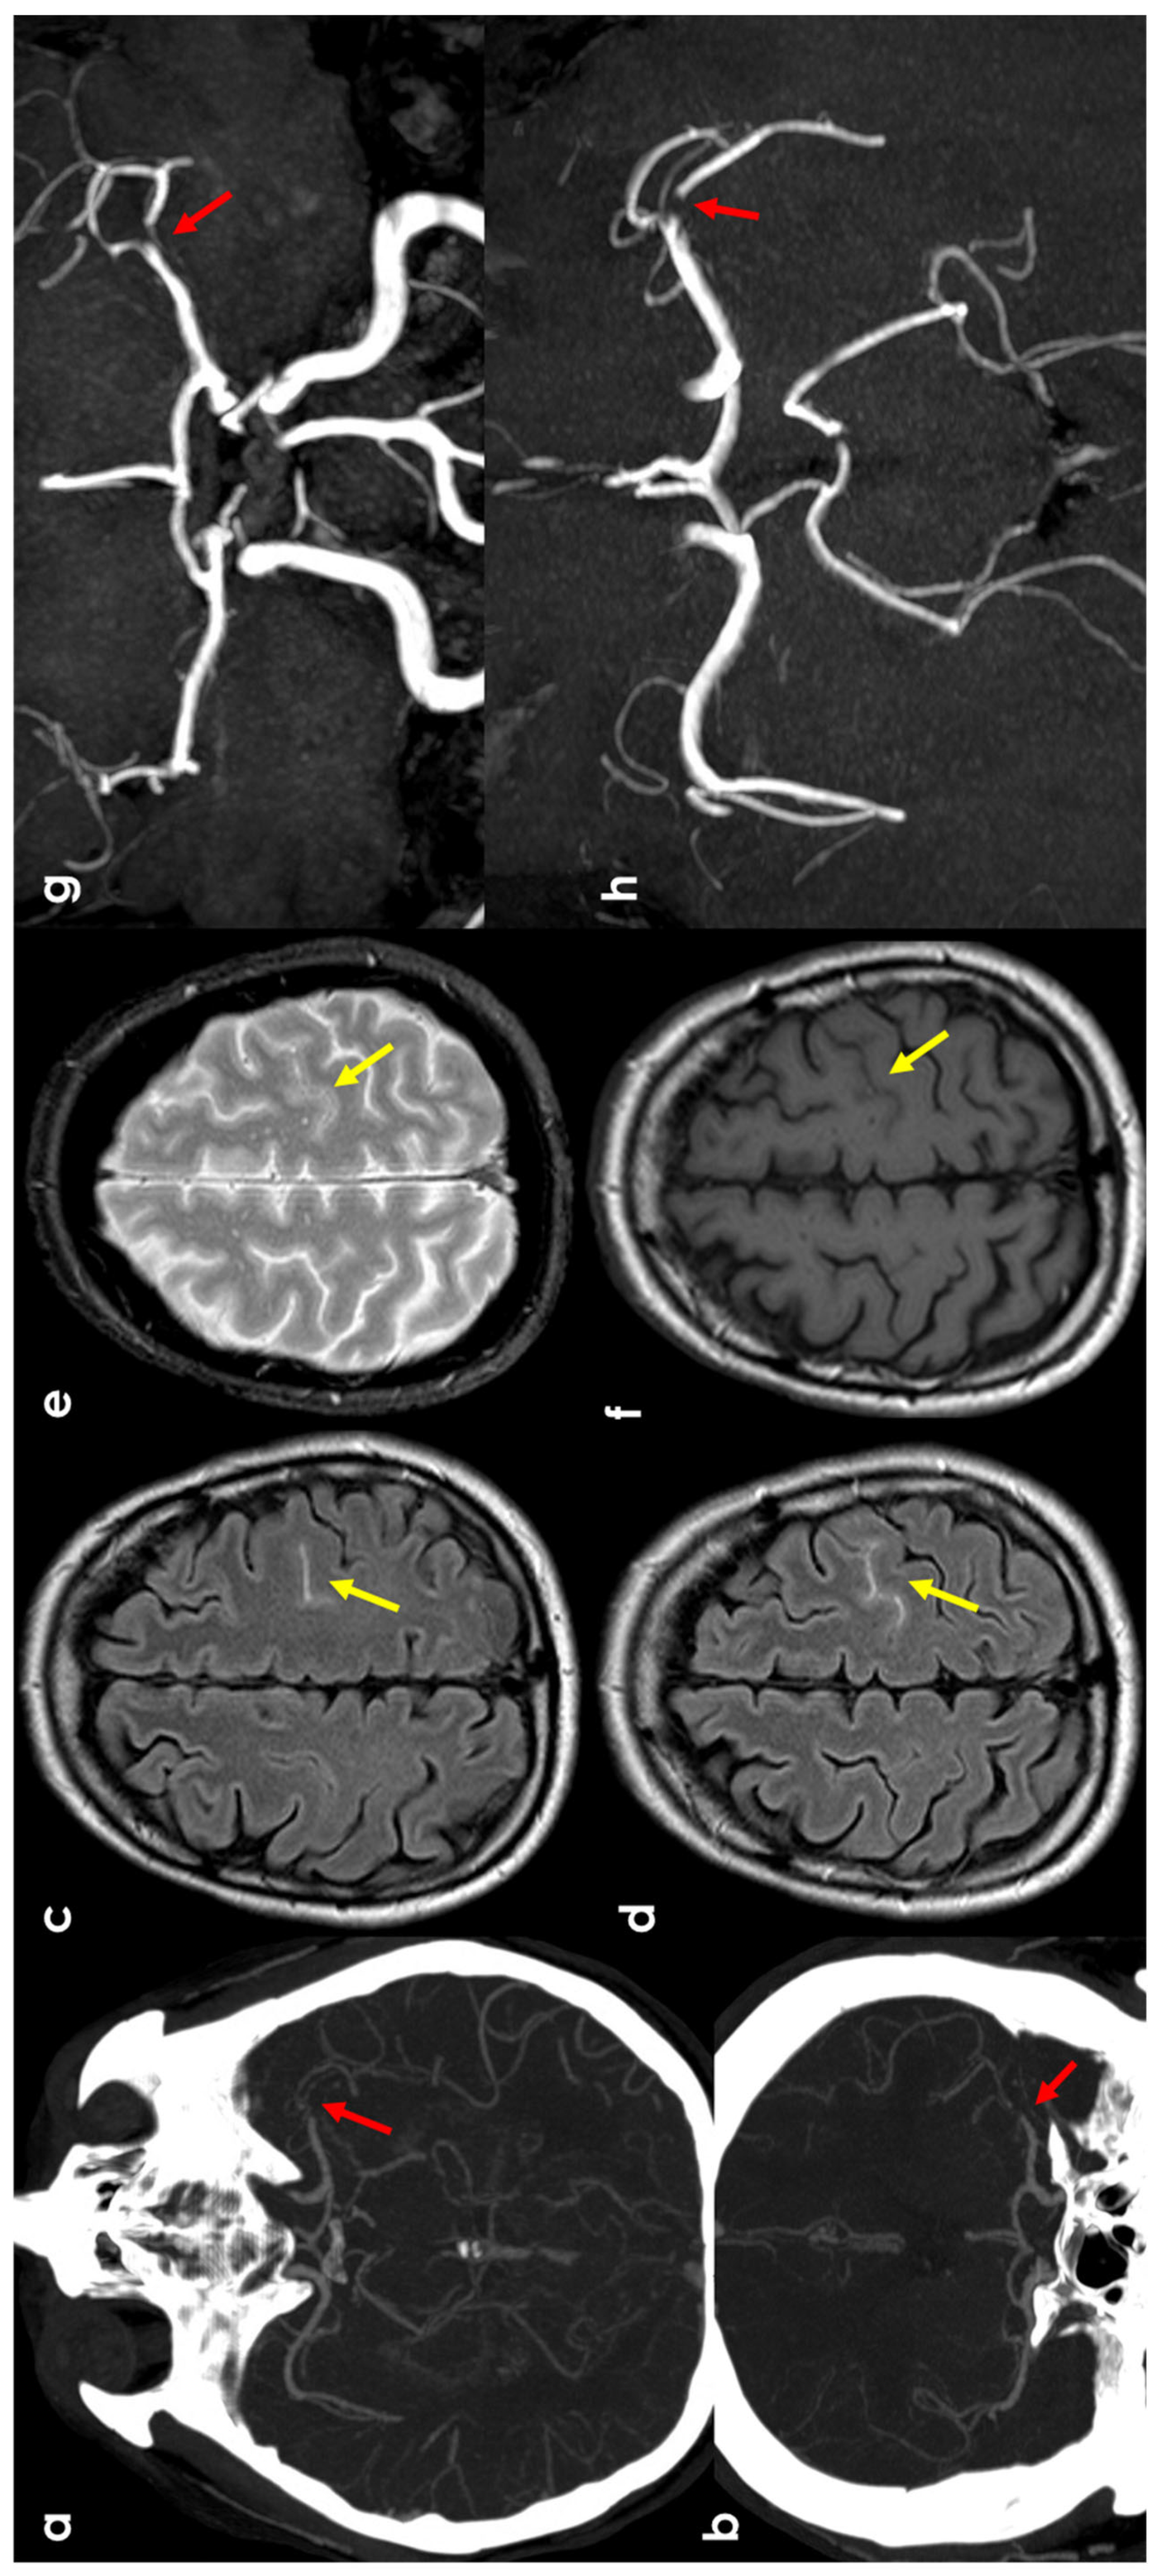

2. Epidemiology and Clinical Presentation

3.2. Hemodynamic Arterial Stenosis

3.3. Infective Endocarditis

3.4. Cerebral Venous Thrombosis

3.5. Primary Central Nervous System Angiitis

3.6. PRES/RCVS